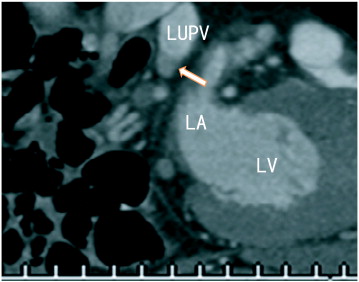

Sagittal images showed an occlusion of the lower branch of the left upper ...

Fig. 2.

Sagittal images showed an occlusion of the lower branch of the left upper pulmonary vein (LUPV) as little contrast enhancements (arrow). LA; left atrium, LUPV; left upper pulmonary vein, LV; left ventricle.

The patient was a 78 year-old-male with hyperlipidemia and PAF. He had been treated with bezafibrate (100 mg 2T bid), but no previous treatment with warfarin or new oral anticoagulants (NOAC) had been performed. The electrocardiogram (ECG) showed normal sinus rhythm, normal axis and normal heart rate (74 beats/min). Serum D-dimer level was < 0.5 μg/ml (normal; < 1.0 μg/ml), the activity of protein S was 124% (normal; 60–150%), and the activity of protein C was 72% (normal; 64–146%). The patient had no symptoms of lung cancer or cerebral infarction. The patient had no lung surgery or catheter ablation. 64-MDCT was performed for the evaluation of chest pain. 64-MDCT illustrated no coronary artery stenosis, but illustrated thrombi in the lower branch of the left upper pulmonary vein (LUPV) (Fig. 1; coronal and Fig. 2; sagittal) as the defect of contrast enhancements. After three month dabigatran therapy, PVT did not dissolve significantly.